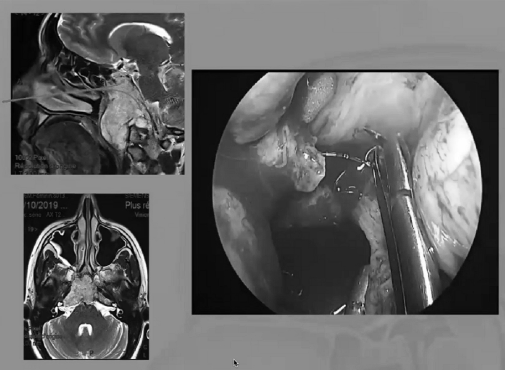

▼下图所示案例肿瘤看着很大,然后用30度、45度甚至70度的内镜,我们有很多带角度的器械,利用这些器械就可以切除肿瘤。可以先切开黏膜,然后把蝶窦内的黏膜推开,然后进入肿瘤。目前我们正在努力的开发这方面的器械,没有这些器械我们是做不了手术的。

▼下面就是我所说的有角度的器械,然后我们用脂肪来修补,我们在内镜下做缝合,在内镜下做缝合很复杂难度很大,所以很花时间,但是它是值得的。

显微镜+内镜“双镜联合”处理颅颈交界区肿瘤

选择好的入路是重要的,神经内镜只是一个工具,它对于某些适应症来说是好的,但不是对全部情况都合适。一些情况下可能需要神经内镜联合显微镜手术治疗。

颅底手术的前提是到达颅底深的区域。为此通常有两种选择。要么你创建一个大的手术通路,但会增加病人的手术风险,因为你暴露了更多的组织结构。另外则是尝试缩小手术通路,为了在内部仍然拥有良好的视野,通常可以使用内窥镜来增加手术视野。所以在福洛里希教授所做的多数手术中,内窥镜是手术中必备的,福洛里希教授使用它来观察开颅手术中未暴露的结构。内窥镜配合显微镜几乎是颅底手术的组合,因为颅底手术的操作深度,内窥镜是颅底手术中必备的工具。